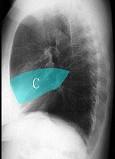

如图所示正常胸部X线影像图像上,该英文字母所代表的肺段为 ( )A.尖段B.后段C.尖后段D.舌叶上段E.前段

问题 如图所示正常胸部X线影像图像上,该英文字母所代表的肺段为 ( )

选项 A.尖段 B.后段 C.尖后段 D.舌叶上段 E.前段

答案 D